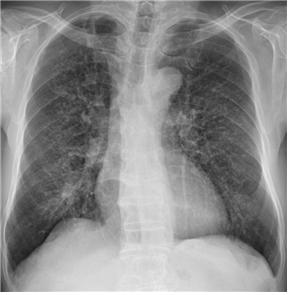

![폐증 환자의 X-ray 검사 사진. 폐에 분진이 침착하여 폐 세포에 염증과 섬유화가 일어난 상태로, 갈비뼈 사이로 하얗게 점처럼 보이는 진폐성 음영을 관찰할 수 있다. [사진=서울성모병원]](https://cdn.industrynews.co.kr/news/photo/201801/21020_11224_150.png)

가톨릭대학교 서울성모병원 명준표 직업환경의학과 교수 연구팀은 2011년 5월부터 6년간 기존 진폐증 판정자 1,200명의 영상을 활용한 딥러닝 연구결과 약 95%의 진단 정확도를 확인했다고 밝혔다. 진폐증은 분진 노출로 폐 세포에 염증과 섬유화가 일어나는 질환이다.